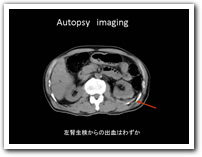

死亡時画像診断(Autopsy imaging)におけるチェックシートの